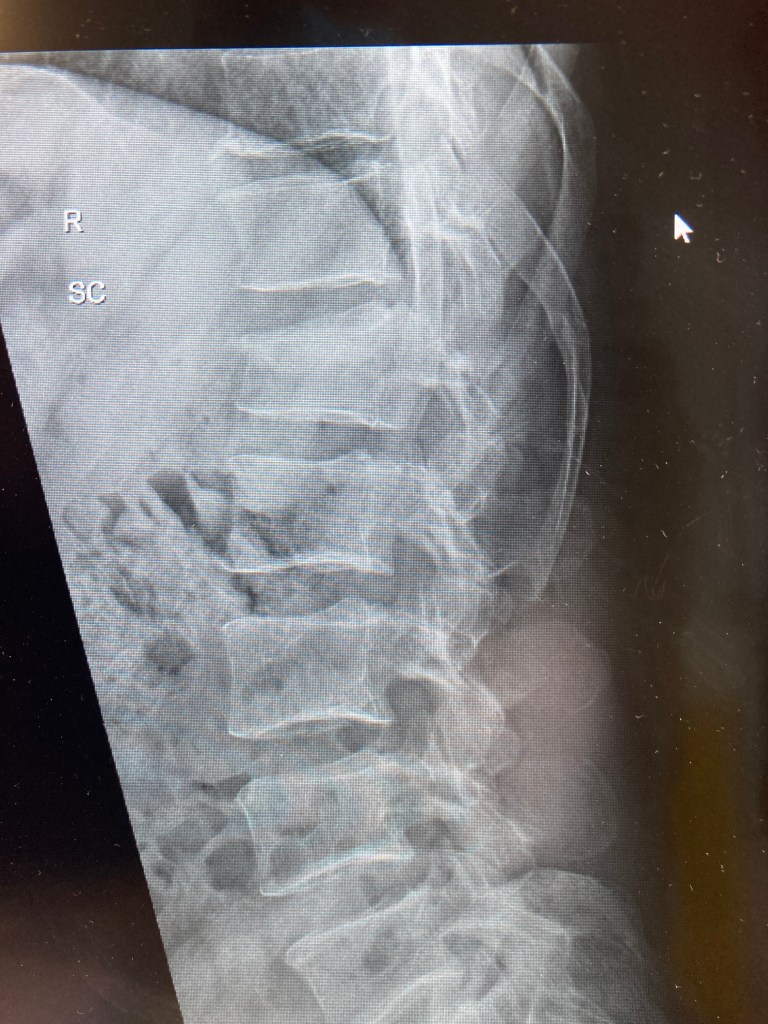

I was back in the hospital today. Arrived early, at about 8am. Still, the outpatients department was bustling with staff, and crocks like me. I had hardly taken my seat when I was asked to head on down to the x-ray department for a scan on my wrist. Oh good… and what about my back? Sorry? Yes, my back; that should be x-rayed as well? Sorry, it’s not listed here…

Ho, hum. I went down anyway, and they dutifully scanned the wrist in its cast. I asked him about the back. No dice, without that little slip of paper. He did try to ring back up to the OPD, but there were no doctors in until nine. I returned back to my seat, and met Dave, the young doctor who had looked after me in the ED and had seen me a few weeks ago. I mentioned the lack of spine scans, and he shook his head and sighed, and within minutes, I was heading back down to the x-ray department for a second set of scans.

Dave reappears to explain that the wrist scans were a little grainy, so they send me back down to the x-ray department for a third time. I should be getting frequent flyer miles. Though I suppose I mustn’t grumble… (it’s all part of the health service we pay for in taxes), and indeed, I don’t grumble, despite Dave apologising several times, I laugh it off, and point out that I’m really not doing anything else at the moment, and I have four hours in the meter outside. We’re all good.

The upshot of all this scanning is that things are going in the right direction. The cast will hopefully come off in two weeks, which is sooner than I thought. But I won’t object. The back brace can be relaxed around the house, and just worn if I am heading out or doing any activities like dog walking. And in about four to six weeks, we can start doing some actual exercises, such as yoga (Dave’s suggestion), and swimming. In the meantime, I will do some work on the spin bike upstairs, starting tomorrow.

I would love to have an MRI as well, to see what’s going with the discs, because things could obviously get worse if one or two were to prolapse. But I don’t think the hospital will stretch to that. As of yet, Dave hasn’t said I can’t run. Though he hasn’t really enthused about it either. I am keen to get back out there, obviously. But not if it could have repercussions. And so we wait.